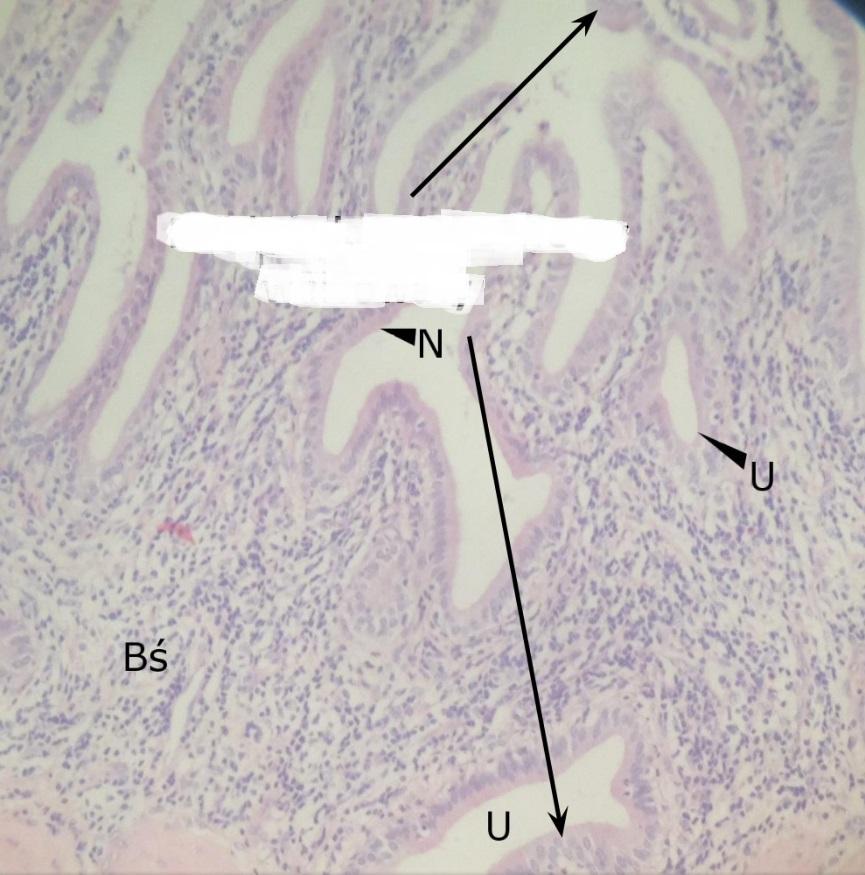

nabłonek jednowarstwowy walcowaty (pęcherzyk żółciowy)

Pytanie 459

uchyłek błony śluzowej (pęcherzyk żółciowy)

Pytanie 460

blaszka właściwa błony śluzowej - brak jest błony podśluzowej! (pęcherzyk żółciowy)